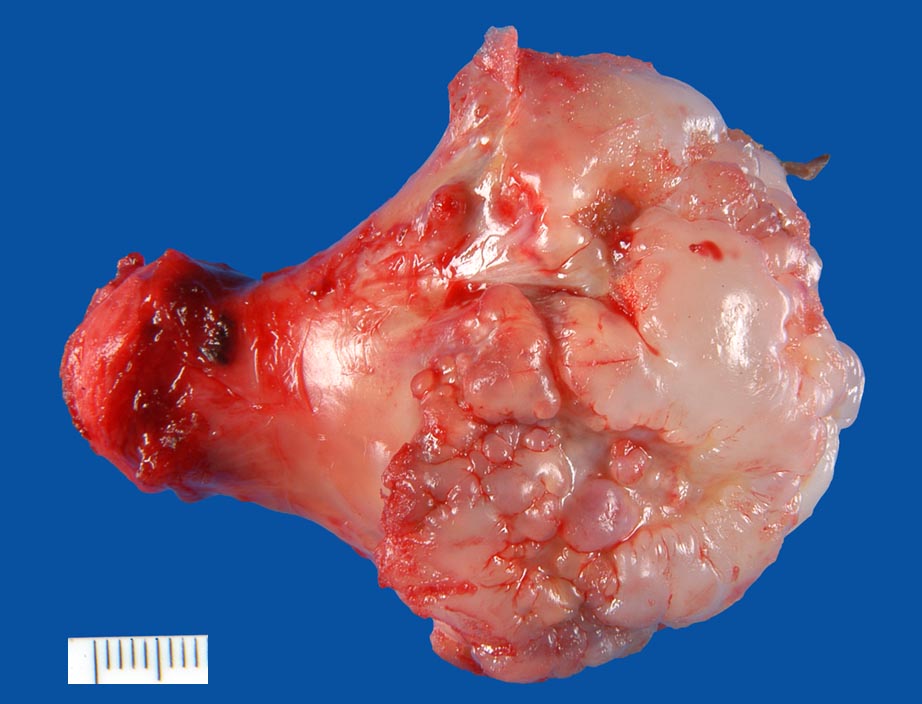

Osteochondrome sind breitbasig dem Knochen aufsitzende oder gestielte knöcherne Tumoren, die von einer 1-6mm dicken Kappe aus hyalinem Knorpel bedeckt werden. Zwischen Knorpel und Knochen liegt eine Zone enchondraler Ossifikation, die der normalen Wachstumsfuge ähnelt und den Ausgangspunkt für die Grössenzunahme des Tumors bei noch nicht abgeschlossenem Skelettwachstum darstellt. Der hyaline Knorpel wirkt etwas unorganisiert und ist bedeckt von einer dünnen Schicht Perichondrium.

Eine Knorpeldicke von über 2cm und erneute Grössenzunahme oder Auftreten von Schmerzen nach Abschluss des Skelettwachstums sind Zeichen einer möglichen malignen Transformation in ein sekundäres (epiexostotisches) Chondrosarkom (weniger als 1% der Fälle). Frakturen des Stiels mit ausgeprägter Kallusbildung oder die Entwicklung einer Pseudarthrose können vorkommen. Auf der Knorpeloberfläche kann als Antwort auf mechanische Reizung eine Bursa entstehen, die ein Grössenwachstum des Osteochondroms vortäuschen kann. Multiple Osteochondrome stellen ein eigenes Krankheitsbild dar, das autosomal-dominant vererbt wird (= Exostosenkrankheit) und mit einem etwas höheren Entartungsrisiko assoziiert ist. Eine Exostosenkrankheit kann diagnostiziert werden, wenn mehr als ein Osteochondrom vorliegt.

Osteochondrome (Synonym: kartilaginäre Exostosen) sind nach den nicht-ossifizierenden Knochenfibromen (NOF) die häufigsten gutartigen Knochentumoren. Betroffen sind meist Patienten in den ersten zwei Lebensdekaden.

Meistens sind Osteochondrome asymptomatisch und fallen als Zufallsbefund im Röntgenbild oder als schmerzlose Knochenverdickung auf. Schmerzen können durch Traumatisierung oder Druck auf Muskeln, Sehnen oder Gefäss-Nervenbündel entstehen.

Im konventionellen Röntgenbild lassen sich gestielte und breitbasige Osteochondrome unterscheiden, wobei letztgenannte Formen immer vom Gelenk weggerichtet sind. Ein wichtiges Charakteristikum ist, dass die Spongiosa des Osteochondroms mit der Spongiosa des ortsständigen Knochens in Verbindung steht und die Läsion nicht einfach nur der Kompakta aufsitzt. Die Knorpelkappe ist im konventionellen Röntgenbild (> 5033) nur angedeutet erkennbar, kann aber im CT, MRI oder im Ultraschall dargestellt und ausgemessen werden. In der Mehrzahl der sporadischen aber v.a. der hereditären Osteochondrome lassen sich biallelische Inaktivierungen des EXT1 oder EXT2 Gens nachweisen, was die neoplastische Genese der Läsionen unterstreicht.